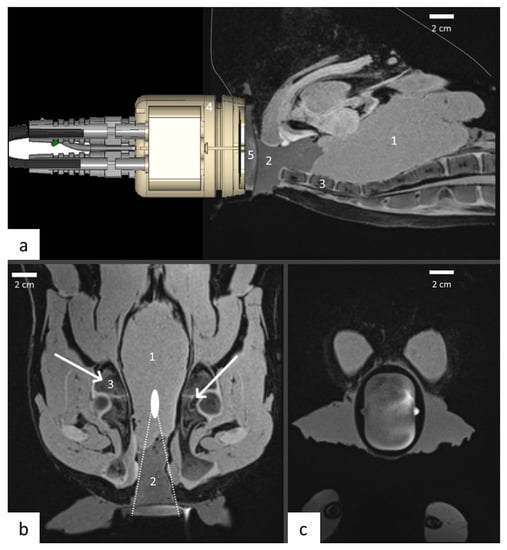

2.5. MRI Guidance of Local Hyperthermia

2.7. Ex-Vivo Studies

3.1. Transducer Design

- Guillemin, P.C.; Dipasquale, G.; Uiterwijk, J.W.; Jaccard, M.; Lorton, O.; Tsoutsou, P.; Gariani, J.; Poletti, P.-A.; Salomir, R.; Zilli, T. Magnetic resonance-guided ultrasound hyperthermia for prostate cancer radiotherapy: An immobilization device embedding the ultrasound applicator. J. 3D Print. Med. 2022, 6, 55–67. [Google Scholar] [CrossRef]